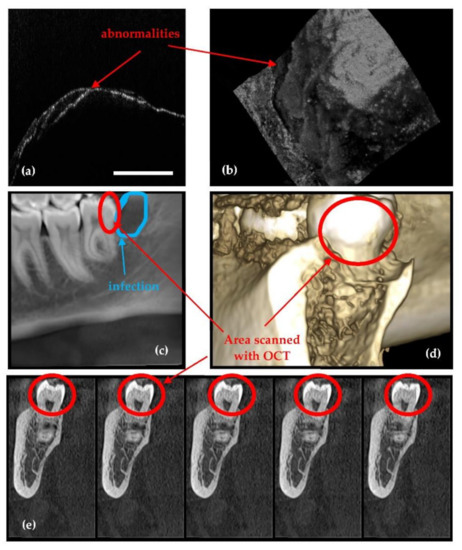

- Because it is using IR laser radiation, OCT does not penetrate metals, although studies of their roughness can be made [46] and, as shown in Figure 4, OCT can provide images near dental crowns, while 3D CBCT for example cannot achieve such images. Also, we have demonstrated that OCT can replace the gold standard of SEM in the study of metallic fractures [47,48]. Therefore, a subject of future work in our groups refers to OCT studies of metallic parts included in the oral cavity, for example dental implants.

- Erdelyi, R.-A.; Duma, V.-F.; Sinescu, C.; Dobre, G.M.; Bradu, A.; Podoleanu, A. Dental Diagnosis and Treatment Assessments: Between X-rays Radiography and Optical Coherence Tomography. Materials 2020, 13, 4825. [Google Scholar] [CrossRef]